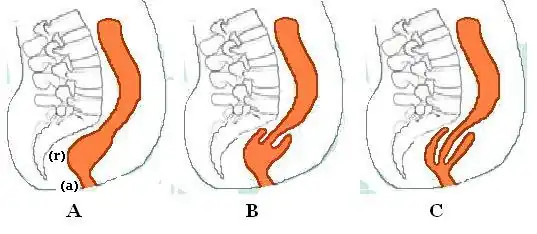

| A. full thickness external rectal prolapse, and B. mucosal prolapse. Note circumferential arrangement of folds in full thickness prolapse compared to radial folds in mucosal prolapse.[1] | |

B. Recto-rectal intussusception

C. Recto-anal intussusception

Rectal prolapse may be confused easily with prolapsing hemorrhoids.[5] Mucosal prolapse also differs from prolapsing (3rd or 4th degree) hemorrhoids, where there is a segmental prolapse of the hemorrhoidal tissues at the 3, 7 and 11 o'clock positions.[13] Mucosal prolapse can be differentiated from a full thickness external rectal prolapse (a complete rectal prolapse) by the orientation of the folds (furrows) in the prolapsed section. In full thickness rectal prolapse, these folds run circumferential. In mucosal prolapse, these folds are radially.[10] The folds in mucosal prolapse are usually associated with internal hemorrhoids. Furthermore, in rectal prolapse, there is a sulcus present between the prolapsed bowel and the anal verge, whereas in hemorrhoidal disease there is no sulcus.[3] Prolapsed, incarcerated hemorrhoids are extremely painful, whereas as long as a rectal prolapse is not strangulated, it gives little pain and is easy to reduce.[5]

Diagnosis

Mucosal prolapse can be differentiated from a full thickness external rectal prolapse (a complete rectal prolapse) by the orientation of the folds (furrows) in the prolapsed section. In full thickness rectal prolapse, these folds run circumferential. In mucosal prolapse, these folds are radially.[10] The folds in mucosal prolapse are usually associated with internal hemorrhoids.[21]